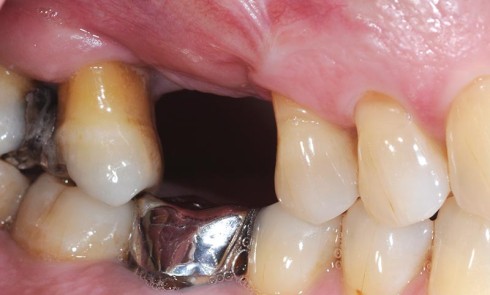

Article réservé à nos abonnés Restauration d’une dent dépulpée dans le secteur postérieur

La communication avec le laboratoire C’est une étape connue pour être importante dansla réussite d’une restauration prothétique. Ellea pour but...